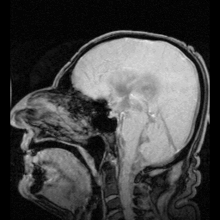

![]() The ventricular system accounts for the production and circulation of cerebrospinal fluid. | |

The ventricular system is a set of four interconnected cavities (ventricles) in the brain, where the cerebrospinal fluid (CSF) is produced. Within each ventricle is a region of choroid plexus, a network of ependymal cells involved in the production of CSF. The ventricular system is continuous with the central canal of the spinal cord (from the fourth ventricle) allowing for the flow of CSF to circulate. All of the ventricular system and the central canal of the spinal cord is lined with ependyma, a specialised form of epithelium.

Ventricles

The four cavities of the human brain are called ventricles.[1] The two largest are the lateral ventricles in the cerebrum; the third ventricle is in the diencephalon of the forebrain between the right and left thalamus; and the fourth ventricle is located at the back of the pons and upper half of the medulla oblongata of the hindbrain. The ventricles are concerned with the production and circulation of cerebrospinal fluid[2]

The ventricles are filled with cerebrospinal fluid (CSF) which bathes and cushions the brain and spinal cord within their bony confines. CSF is produced by modified ependymal cells of the choroid plexus found in all components of the ventricular system except for the cerebral aqueduct and the posterior and anterior horns of the lateral ventricles. CSF flows from the lateral ventricles via the foramina of Monro into the third ventricle, and then the fourth ventricle via the cerebral aqueduct in the brainstem. From the fourth ventricle it can pass into the central canal of the spinal cord or into the cisterns of the subarachnoid space via three small foramina: the central foramen of Magendie and the two lateral foramina of Luschka.